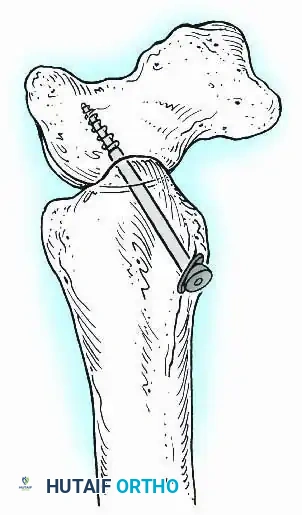

Knee Arthrodesis

While total knee arthroplasty (TKA) is the definitive treatment for knee osteoarthritis, knee arthrodesis remains a critical salvage procedure. The primary indications are a chronically infected TKA that has failed two-stage revision, massive extensor mechanism disruption, severe neuropathic arthropathy, and tumor resection.

Positioning and Technique

The optimal position for knee arthrodesis is 10 to 15 degrees of flexion and 5 to 7 degrees of valgus. This slight flexion assists in foot clearance during the swing phase of gait and makes sitting in confined spaces more manageable. A perfectly straight (0 degrees) knee is cosmetically awkward and functionally detrimental, causing a vaulting gait pattern.